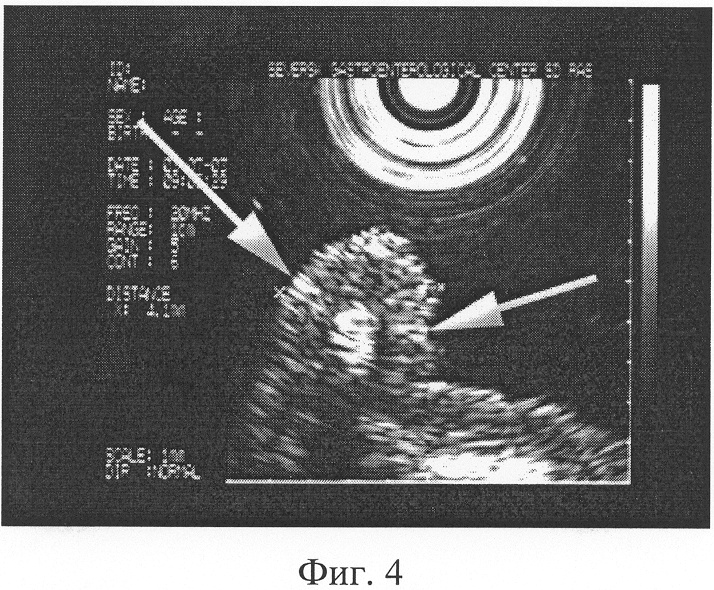

При наличии грубых извитых складок слизистой, их атипической перестройки, ширина которых в теле и антральном отделе желудка более 6 мм, по большой кривизне, в своде и синусе более 10 мм (Фиг.4), соотношении минимальной к максимальной высот желудочной складки от подслизистого слоя, приближающемся 1:1,5, наличии желудочных полей правильной округлой формы, диаметром 3-5 мм (Фиг.5) диагностируют поверхностный гастрит.

12.10.2004 г. проведено обследование согласно предлагаемому способу.

В результате проведенного исследования установлено, что слизистая пищевода обычной окраски. Кардия полностью смыкается. В желудке слизи нет. Слизистая желудка в антральном отделе умеренно гиперемирована, блестящая, дефектов слизистой нет, в антральном отделе желудка складки имеют грубый, извитый характер, ширина складок в антральном отделе желудка от 6 до 8 мм, по большой кривизне складки расположены типично, ширина их не превышает 10 мм (Фиг.4). Соотношение минимальной к максимальной высоте желудочной складки от подслизистого слоя приближается 1:1,5. Желудочные поля имеют неправильную округлую форму диаметром 4 мм (Фиг.5). Привратник сомкнут, проходим. Луковица двенадцатиперстной кишки не деформирована, патологии со стороны двенадцатиперстной кишки нет. Заключение: Хронический поверхностный гастрит, обострение.

Фиг.4. Б-ой А. 36 л. Эндоскопическая гастросонография. Извитые складки слизистой желудка, гиперэхогенные мелкие включения в структуре слизистой, ширина складок в теле и антральном отделе желудка до 6-8 мм, по большой кривизне, в своде и синусе – 10 мм (обозначены стрелками). Соотношение минимальной к максимальной высоте желудочной складки от подслизистого слоя 1:1,5.